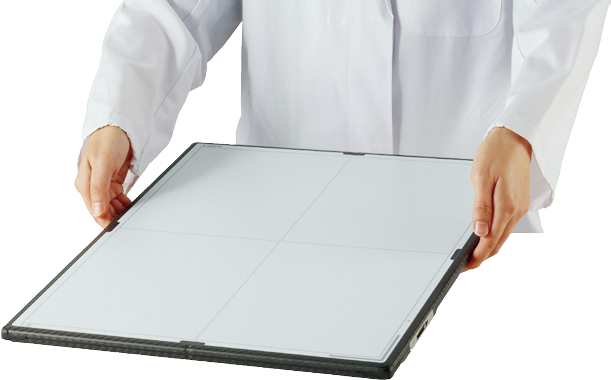

Une meilleure imagerie et des diagnostics plus précis commencent avec Canon CXDI. Chaque système Canon DR possède l'extraordinaire qualité et fiabilité du leader mondial de la technologie novatrice.

Capteurs Canon CXDI (pdf)Configuration des capteurs (pdf)